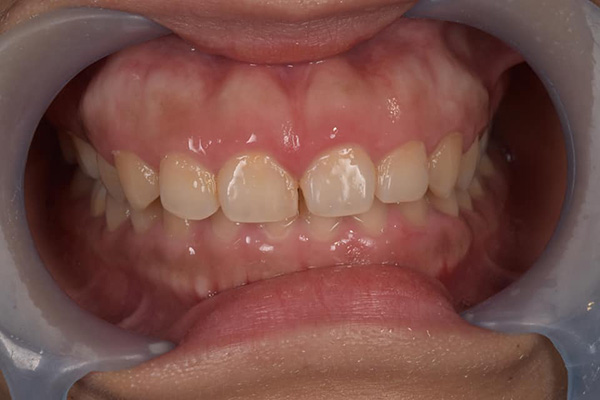

牙周病初期治療(無手術,治療前)![]() |

牙周病初期治療(無手術,治療後)![]() |